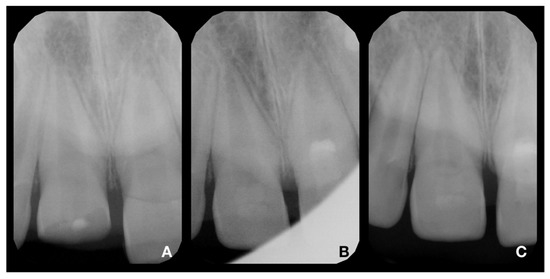

2.2. Partial Pulpotomy and Adhesive Reattachment of Tooth 11

2.3. Deep Pulpotomy and Adhesive Reattachment of Tooth 21 after Flap Reflection

2.4. Follow-Up